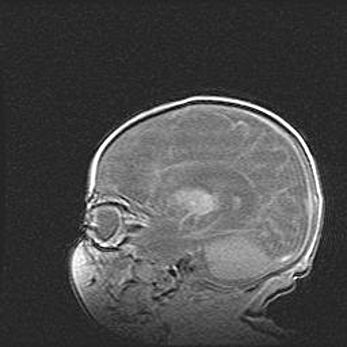

Мальформация Денди-Уокера. Киста задней черепной ямки.

Агенезия мозолистого тела.

Возраст: 2,5 месяца

Вес: 2420 г

Пол: женский

Окружность головы: 37 см

Срок гестации: 32 недели

Мальформация Денди—Уокера — редкий вид патологии ЦНС, представляющий собой врожденный порок развития каудального отдела ствола и червя мозжечка, ведущий к неполному раскрытию срединной (Мажанди) и латеральных (Лушка) апертур IV желудочка мозга. Для этогно синдрома характерна триада симптомов: гипотрофия червя мозжечка и/или полушарий мозжечка, кисты задней черепной ямки, гидроцефалия различной степени. В 70% случаев порок сочетается и с другими аномалиями головного мозга, в частности с агенезией мозолистого тела.